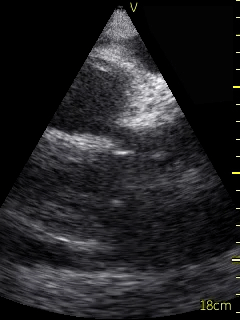

Video 1 (online supplement; Figure 1) demonstrates a parasternal long axis view with the pericardial effusion noted to be posterior to the left ventricle in this view. Video 2 (online supplement; Figure 2) is a short axis view of the heart which is showing that the effusion is surrounding the heart. Video 3 and 4 (online supplements; Figures 3 & 4) demonstrates that the pericardial effusion is present significantly surrounding the apex as well. An echocardiogram confirmed the POCUS findings and cardiology was consulted to conduct a pericardiocentesis, following which the patient’s symptoms resolved. The effusion was thought to be chronic and transudative. In this case, the use of POCUS at the bedside allowed for rapid detection of a large pericardial effusion and subsequent treatment.